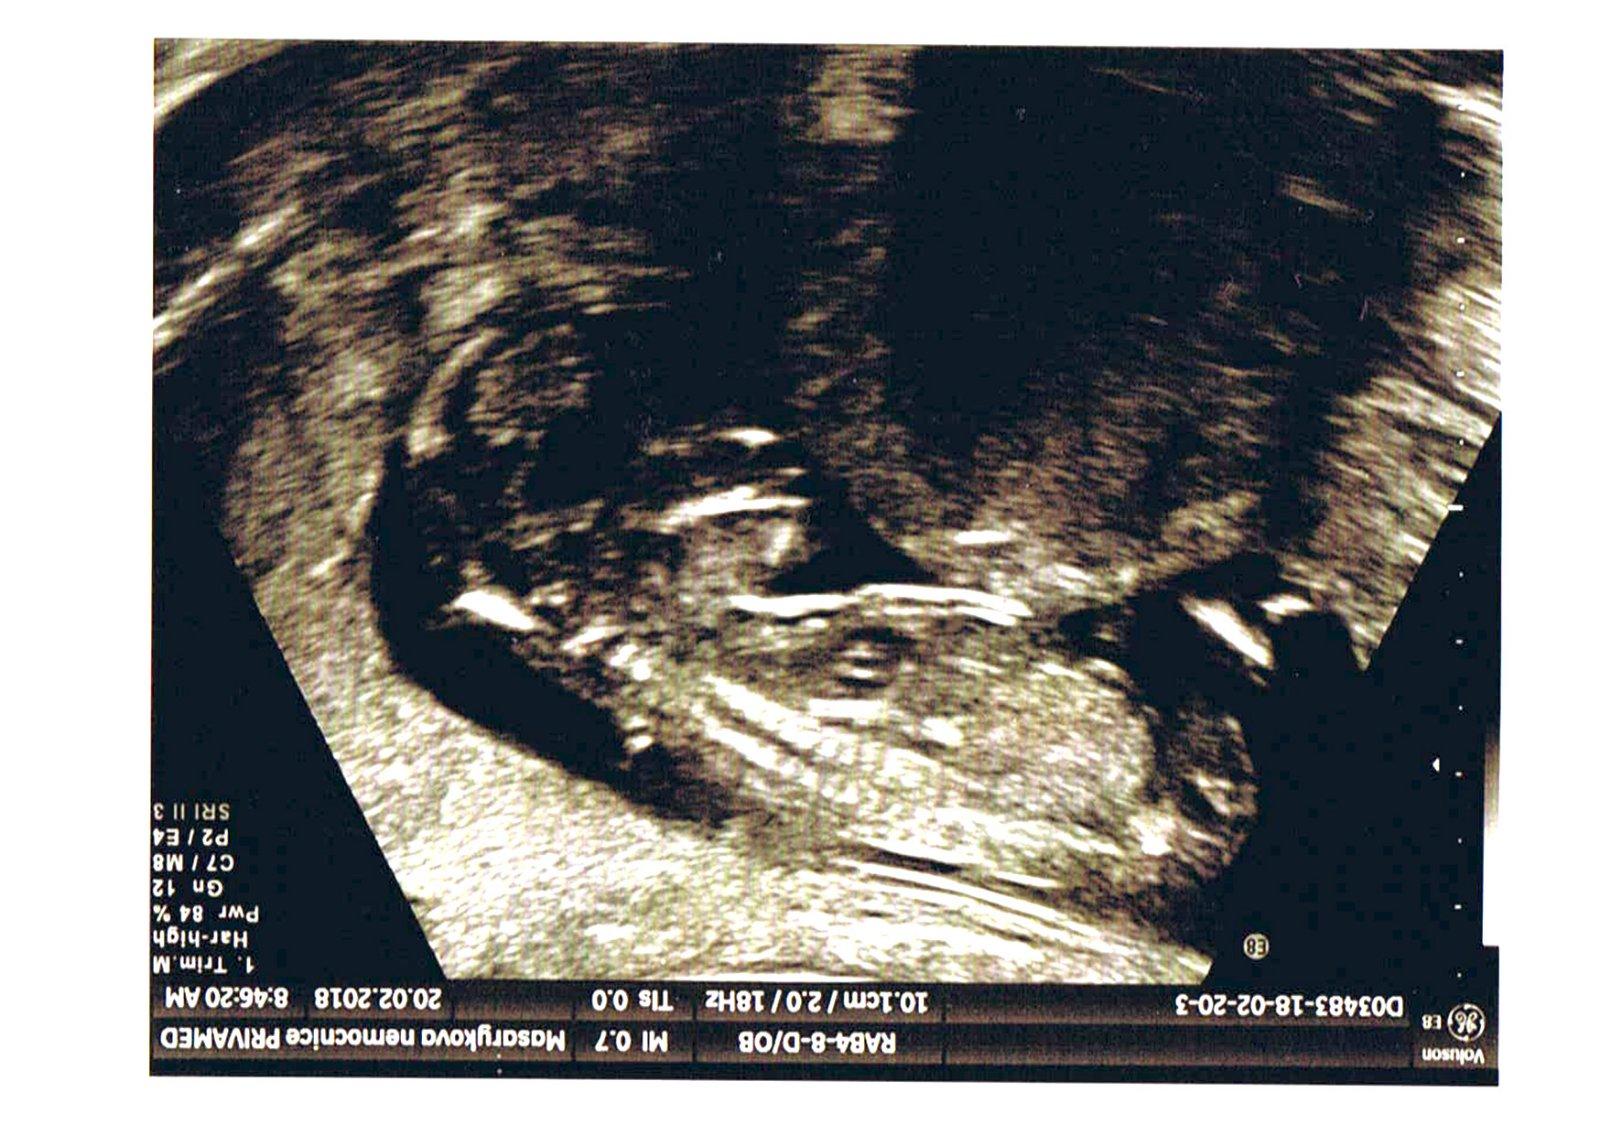

Holky tak po dnesnim 3D ultrazvuku to bude holcicka 😍 a je stejna jako jeji starsi sestricka 😊